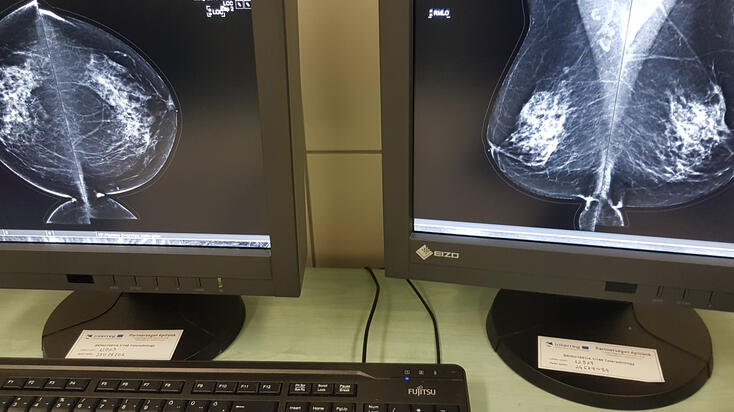

A fejlesztés részeként Miskolcon a már meglévő PACS (Picture Archiving and Communication System) rendszer fejlesztéséhez, míg Királyhelemcen a PACS rendszer bevezetéséhez szükséges informatikai hardver, valamint szoftver elemeket szereztek be. A PACS egy olyan technológia, amely képes kezelni, archiválni, megjeleníteni és megosztani a képi dokumentációt, például a röntgen, a mágneses rezonancia és a CT képeket.

Kostyál László, a Borsod-Abaúj-Zemplén Megyei Központi Kórház és Egyetemi Oktatókórház Képalkotó Diagnosztikai Centrumának osztályvezető főorvosa hangsúlyozta: a szlovák részről nagyobb beruházást jelentett a projekt, „ugyanis ők egy új gépet, egy teljesen új technikát kaptak“, a Borsod megyei egészségügyi intézményben a már meglévő technikának a modernizálása és a felgyorsítása volt a cél, ennek részeként készült 13 új leletező állomás az osztályra.

A fejlesztésnek köszönhetően a képek gyorsan „lejönnek“, azonnal megtekinthetők. Nagyon fontos lenne, hogy a szlovák munkatársak itt - Miskolcon - is gyakorlatot, tudásanyagot szerezzenek, hiszen a megyei kórházban naponta mintegy 130 CT vizsgálat történik, ott pedig 10-15. Eddig mintegy 60-80 leletanyag érkezett Királyhelmecről, itt nem is a mennyiség, hanem a képek minősége, felbontása volt a fontos, hogy kiváló, tökéletesen kiértékelhető legyen valamennyi – tette hozzá.